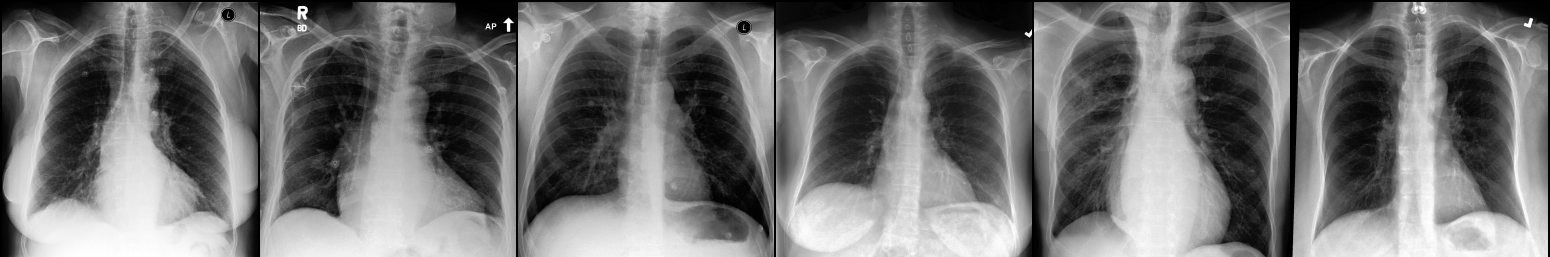

Image Reconstruction. Table 1 shows that the co-training scheme outperforms the \mathcal{E}-training approach in reconstruction accuracy, as indicated by higher PSNR and IW_SSIM scores, highlighting the benefits of joint optimization for enhancing reconstruction quality. The results are further validated by the visual comparison in Fig. 2, where the co-training scheme recovers input images with finer details and higher fidelity. In contrast, the \mathcal{E}-training scheme exhibits noticeable discrepancies when compared to the original images.

Refer to caption

XRX_{R}

Co-training

\mathcal{E}-training

Fig. 2: Reconstruction results. The first row displays the real images XRX_{R}. The last two rows show the reconstructed images X^R\hat{X}_{R} produced by the proposed co-training scheme and the \mathcal{E}-training scheme, respectively.